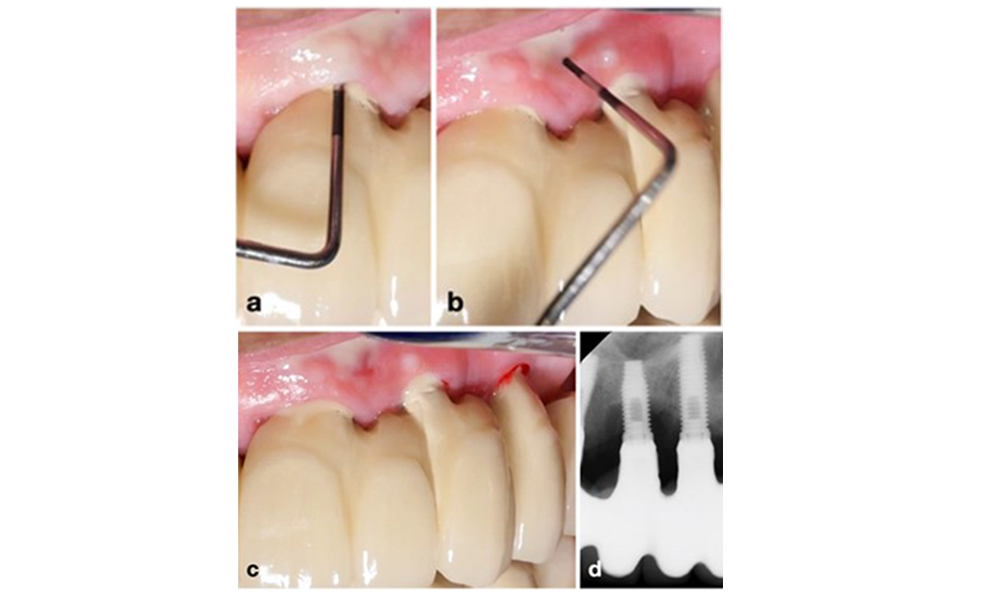

The World Workshop on the Classification of Periodontal and Peri‐Implant Diseases and Conditions from 2017 established diagnostic criteria for peri-implant mucositis and peri-implantitis (Renvert et al. 2018). Peri-implant mucositis is defined as (1) presence of inflammation around the implant (i.e., redness, swelling, line or drop of bleeding within 30 seconds of probing), combined with (2) no additional bone loss after initial healing (figure 1).

Peri-implantitis is identified by (1) signs of inflammation similar to mucositis, (2) radiographic evidence of bone loss after initial healing and (3) an increase in probing depth compared to measurements taken shortly after placing the prosthetic reconstruction (figure 2). In the absence of previous radiographs, radiographic bone level of ≥ 3 mm along with bleeding on probing and probing depths ≥ 6 mm, indicates peri‐implantitis.

The expected bone loss after initial healing attributed to marginal bone remodelling, varies based on factors such as the implant system or type. For instance, 1–2 mm bone loss is generally considered “normal” for bone level implants with an external connection (figure 2d, implant in position 23).